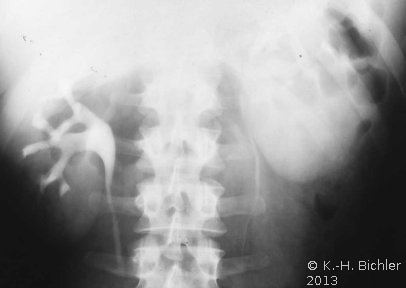

In der Diagnostik der Nierenabszesse (intra- bzw. peri/paranephritisch) spielen neben der Anamnese, Symptomatik (Fieber, Flankenschmerzen) die Laboruntersuchungen: Entzündungsparameter wie BSG und CRP, Kreatinin und Elektrolyte sowie der Urinstatus eine Rolle.

Von Wichtigkeit sind die bildgebenden Verfahren: Sonographie, CT bzw. AUR.

Beispielhaft die Darstellung eines ausgedehnten Nierenabszesses in Sonographie, CT und AUR (Abbildung 6).